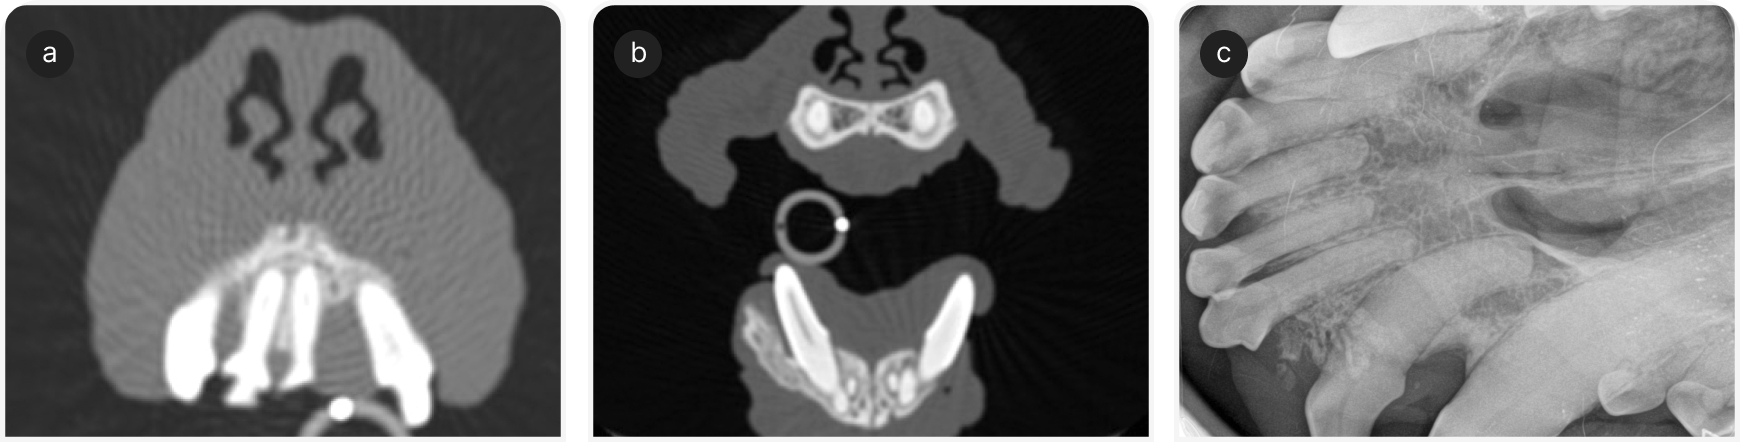

Акантоматозные амелобластомы (АА) — группа одонтогенных опухолей, по основной структуре напоминающих эмалевый орган (Рисунок 5). Опухоли считают вызывающими локальную деструкцию, поскольку они обычно регионарно внедряются в кость и не метастазируют (Рисунок 6). Лечение чаще всего включает в себя хирургическую резекцию единым блоком (en bloc).

Ранее считалось, что после резекции АА часто рецидивирует, но недавнее исследование позволило усомниться в этой точке зрения; в обзоре 263 пациентов с АА признаков рецидива опухоли не было обнаружено ни у одного пациента, даже при том, что у 65,2% пациентов резекция была проведена не в пределах здоровых тканей (7).